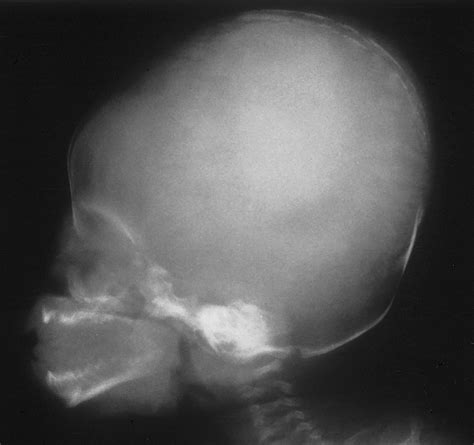

A Baby Skull Xray is a radiographic imaging technique used to visualize the bones of a baby's skull. This non-invasive procedure is essential for diagnosing various conditions, including fractures, deformities, and developmental abnormalities. The X-ray images provide a detailed view of the skull's structure, helping healthcare providers make informed decisions about treatment and care.

Interpreting Baby Skull Xray results requires a trained eye and a deep understanding of pediatric anatomy. Here are some key points to consider:

• Bone Density: The density of the bones can indicate the presence of fractures or other abnormalities.

• Skull Shape: The shape of the skull can provide insights into developmental issues or deformities.

• Fontanelles: The soft spots on a baby’s skull, known as fontanelles, should be checked for proper closure and any signs of swelling or bulging.

• Sutures: The sutures, or the fibrous joints between the skull bones, should be examined for any signs of premature fusion or separation.